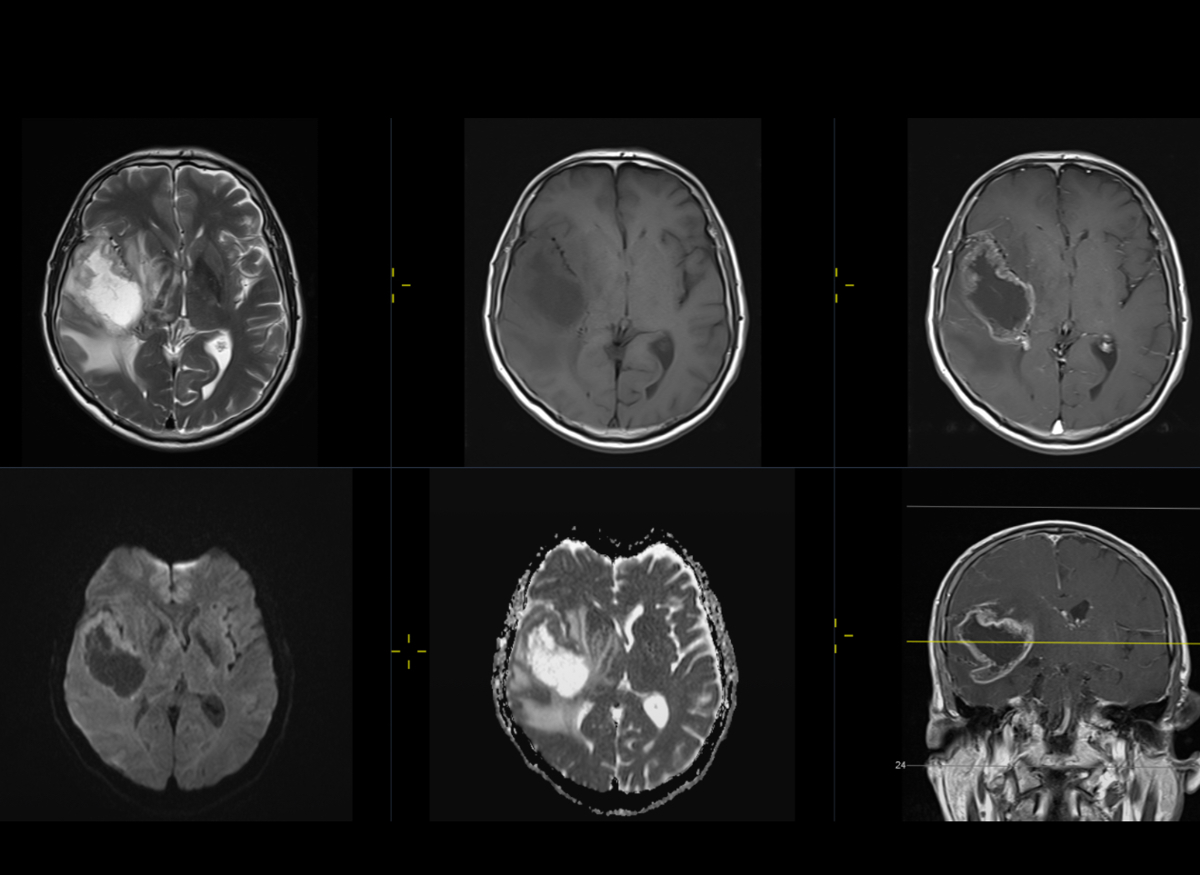

I was diagnosed with glioblastoma, an aggressive and fast-growing form of brain cancer.

Right now, I am preparing for brain surgery to remove as much of the tumour as possible. It is a frightening and overwhelming time for me and my family, as we face both the emotional and physical challenges ahead.